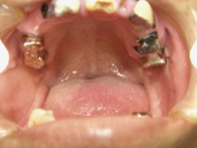

| とても気の毒な状態です。上顎は左上の一番奥の歯しかもちません。

下顎の臼歯部は全滅です。 |

| 見てのとおりとても気の毒な状態です。どこで噛んでいるのかわからない状態です。

左上の糸切り歯はグラグラしていて痛みも伴います。 左上の1・2・3あたりのお肉がいたんでいる状態を見ておいてください。

あとで治っているのがわかります。 |